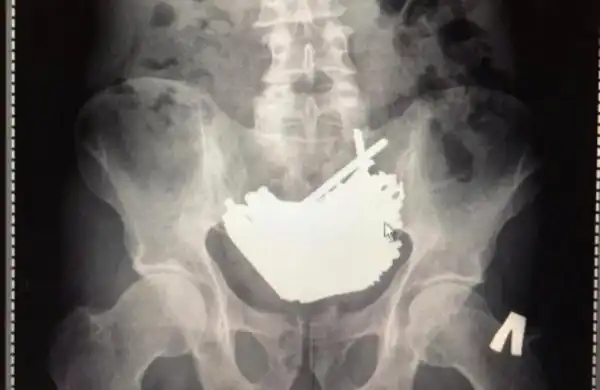

Находка в желудке у заключенного

Из ИК ЕЦ 166/55 (исправительная колония) привезли 35-летнего сидельца с острыми болями в области живота.

Отправили на снимок, а там вот такое чудо – 875 грамм отличных шурупов! 112 штук. Причем носил их он аж четыре месяца.

Зачем глотал? Сам не знает. Просто глотал. Помимо шурупов нашлись еще мелкие гвозди, разрезанные саморезы и даже щипчики для ногтей. Часть в желудке, часть в кишечнике. И большая часть стального груза может быть и вышла бы естественным путем, но этот придурок до кучи проглотил еще и магнит (!!!!!), который всё стянул в один комок.

Через шесть суток после операции чудака выписали и отправили обратно на зону.